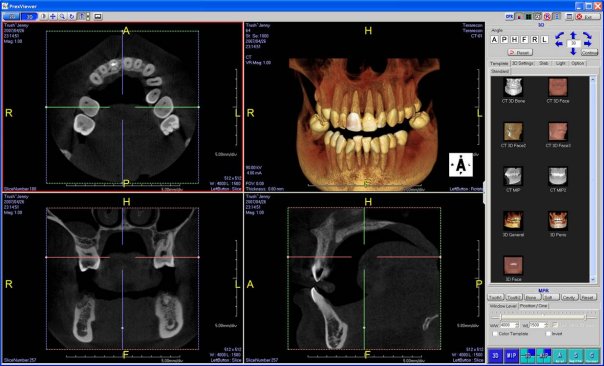

CT Scan Imaging

Computer Guided Implant Planning

Fastest Machine In Taking 19 Second Scan

Prexion 3D CT Scanner

512 Slices Scanner For Accuracy And Better Diagnosis